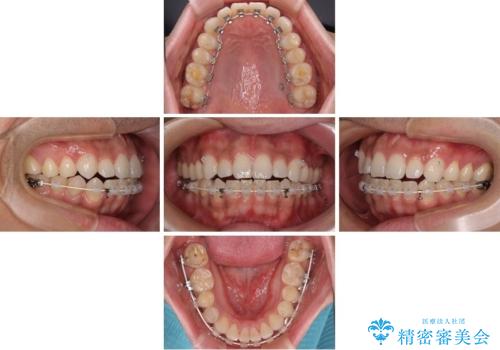

目立たない装置でデコボコを改善 ハーフリンガルによる矯正治療

- 上下顎歯列のデコボコを改善したいとのことで来院された患者様です。

自己管理の大変なインビザラインや、目立つ表側のワイヤー矯正は避けたいとのことで、

上顎だけ裏側装置のハーフリンガルにて矯正しました。

一年と数か月で矯正を終えることができました。

下顎前歯部には後戻り防止のワイヤーを装着しています。